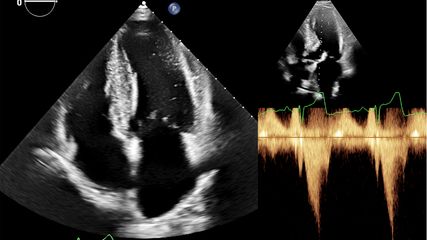

Kinder, die mit kongenitalen Herzvitien geboren werden, erreichen mittlerweile zu mehr 90% das Erwachsenenalter. Mit dem Update ihrer Leitlinie zum Management kongenitaler Vitien bei erwachsenen Patienten liefert die ESC detaillierte Empfehlungen für den Umgang mit den Spätkomplikationen dieser Erkrankungen.

Die Guideline gibt detaillierte Empfehlungen zum Management von Komplikationen kongenitaler Vitien, wie zum Beispiel der pulmonalen Hypertonie, die sich häufig bei Patienten mit Shuntläsionen einstellt. Die Leitlinie betont dabei die Notwendigkeit einer invasiven Abklärung, wenn Patienten mit einer Shuntläsion Hinweise auf erhöhten pulmonalarteriellen Druck zeigen. Das weitere Vorgehen richtet sich nach dem pulmonalen Gefässwiderstand. Ist dieser niedrig, können alle Shunts geschlossen werden. Für höheren Widerstand (mehr als drei Wood‘s Units) gibt die Guideline detaillierte Empfehlungen, welche Shunts unter welchen Umständen verschlossen werden können. Für Patienten, die eine medikamentöse Behandlung ihres Lungenhochdrucks benötigen, werden Empfehlungen in Anlehnung an die PAH-Leitlinie der ESC gegeben – die Therapie soll sich also nach der Risikobewertung richten. Für den Shuntverschluss gibt die Guideline einen Algorithmus vor. Detailliert abgehandelt werden Anomalien des linksventrikulären Ausflusstrakts und der Aortenklappe. Die Frage, ob eine Intervention erforderlich ist, wird anhand der Lokalisation der Läsion, der Symptome (auch unter Provokation) sowie möglicher resultierender Schäden an Ventrikel oder Klappe beantwortet. Neu ist eine Empfehlung für die chirurgische Reparatur der Aortenklappe bei bestimmten Patienten mit Marfan-Syndrom.